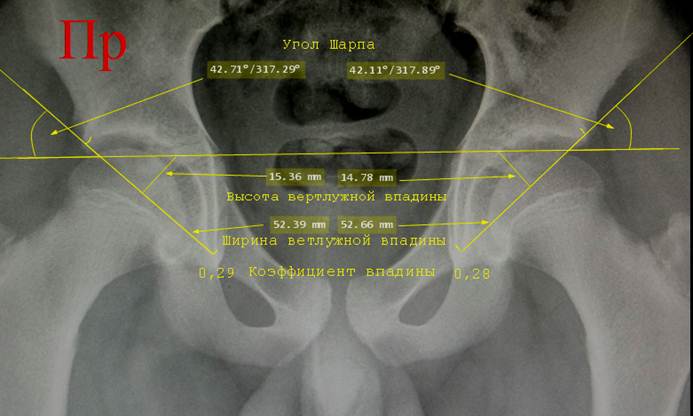

Коэффициент

впадины. Проводят две линии. Первая –

линия входа во впадину - идет от верхнего до нижнего края вертлужной впадины.

Вторая – линия высоты впадины. Это максимально длинный перпендикуляр от линии

входа во впадину к её дну. Он не обязательно должен исходить из середины линии

входа. Обе линии измеряют в миллиметрах,

затем высоту впадины делят на ширину её входа. Полученная цифра и есть

коэффициент впадины.

Угол

Шарпа (угол наклона впадины). Это

угол между линией Хильгенрейнера и линией входа во впадину.

Снимок

таза ребенка 14 лет. Проведена линия

Хильгенрейнера и касательные линии к входам в вертлужную впадину. Угол между

продолжениями этих линий и лииней Хильгенрейнера является углом Шарпа. Отмечены линейные размеры ширины входа и

высоты впадины, рассчитаны коэффициенты впадин.